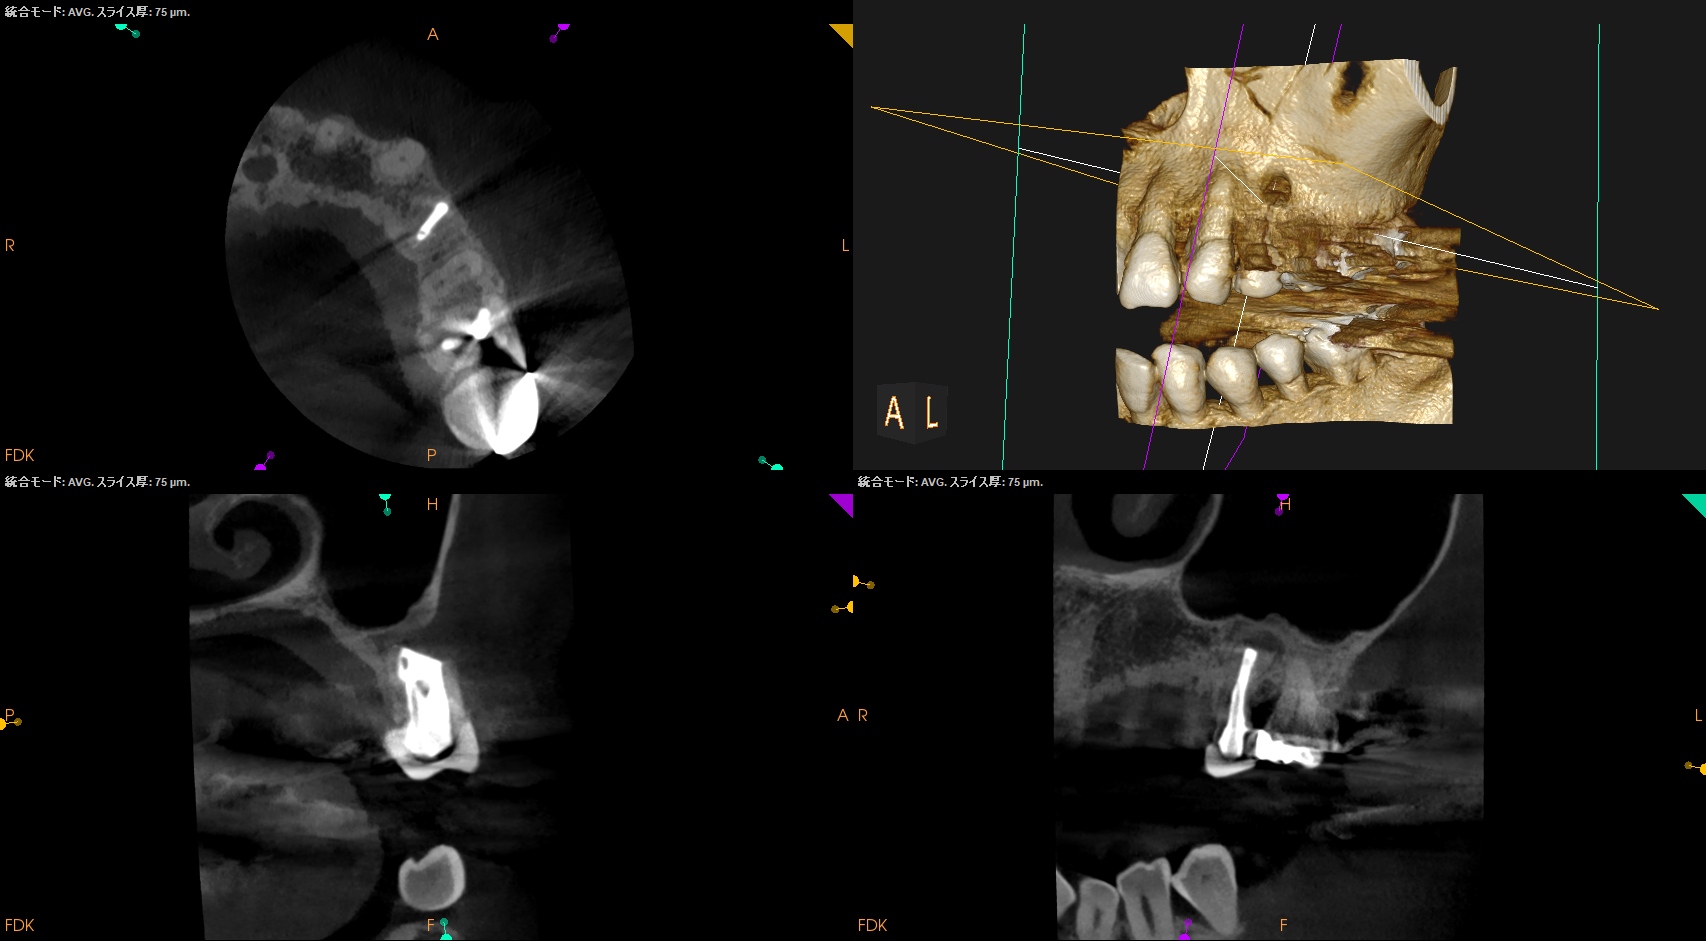

#12 Apicoectomy 6M recall(2026.2.18)

初診時と比較した。

問題は大きく解決している。

最終補綴も問題がないだろう。